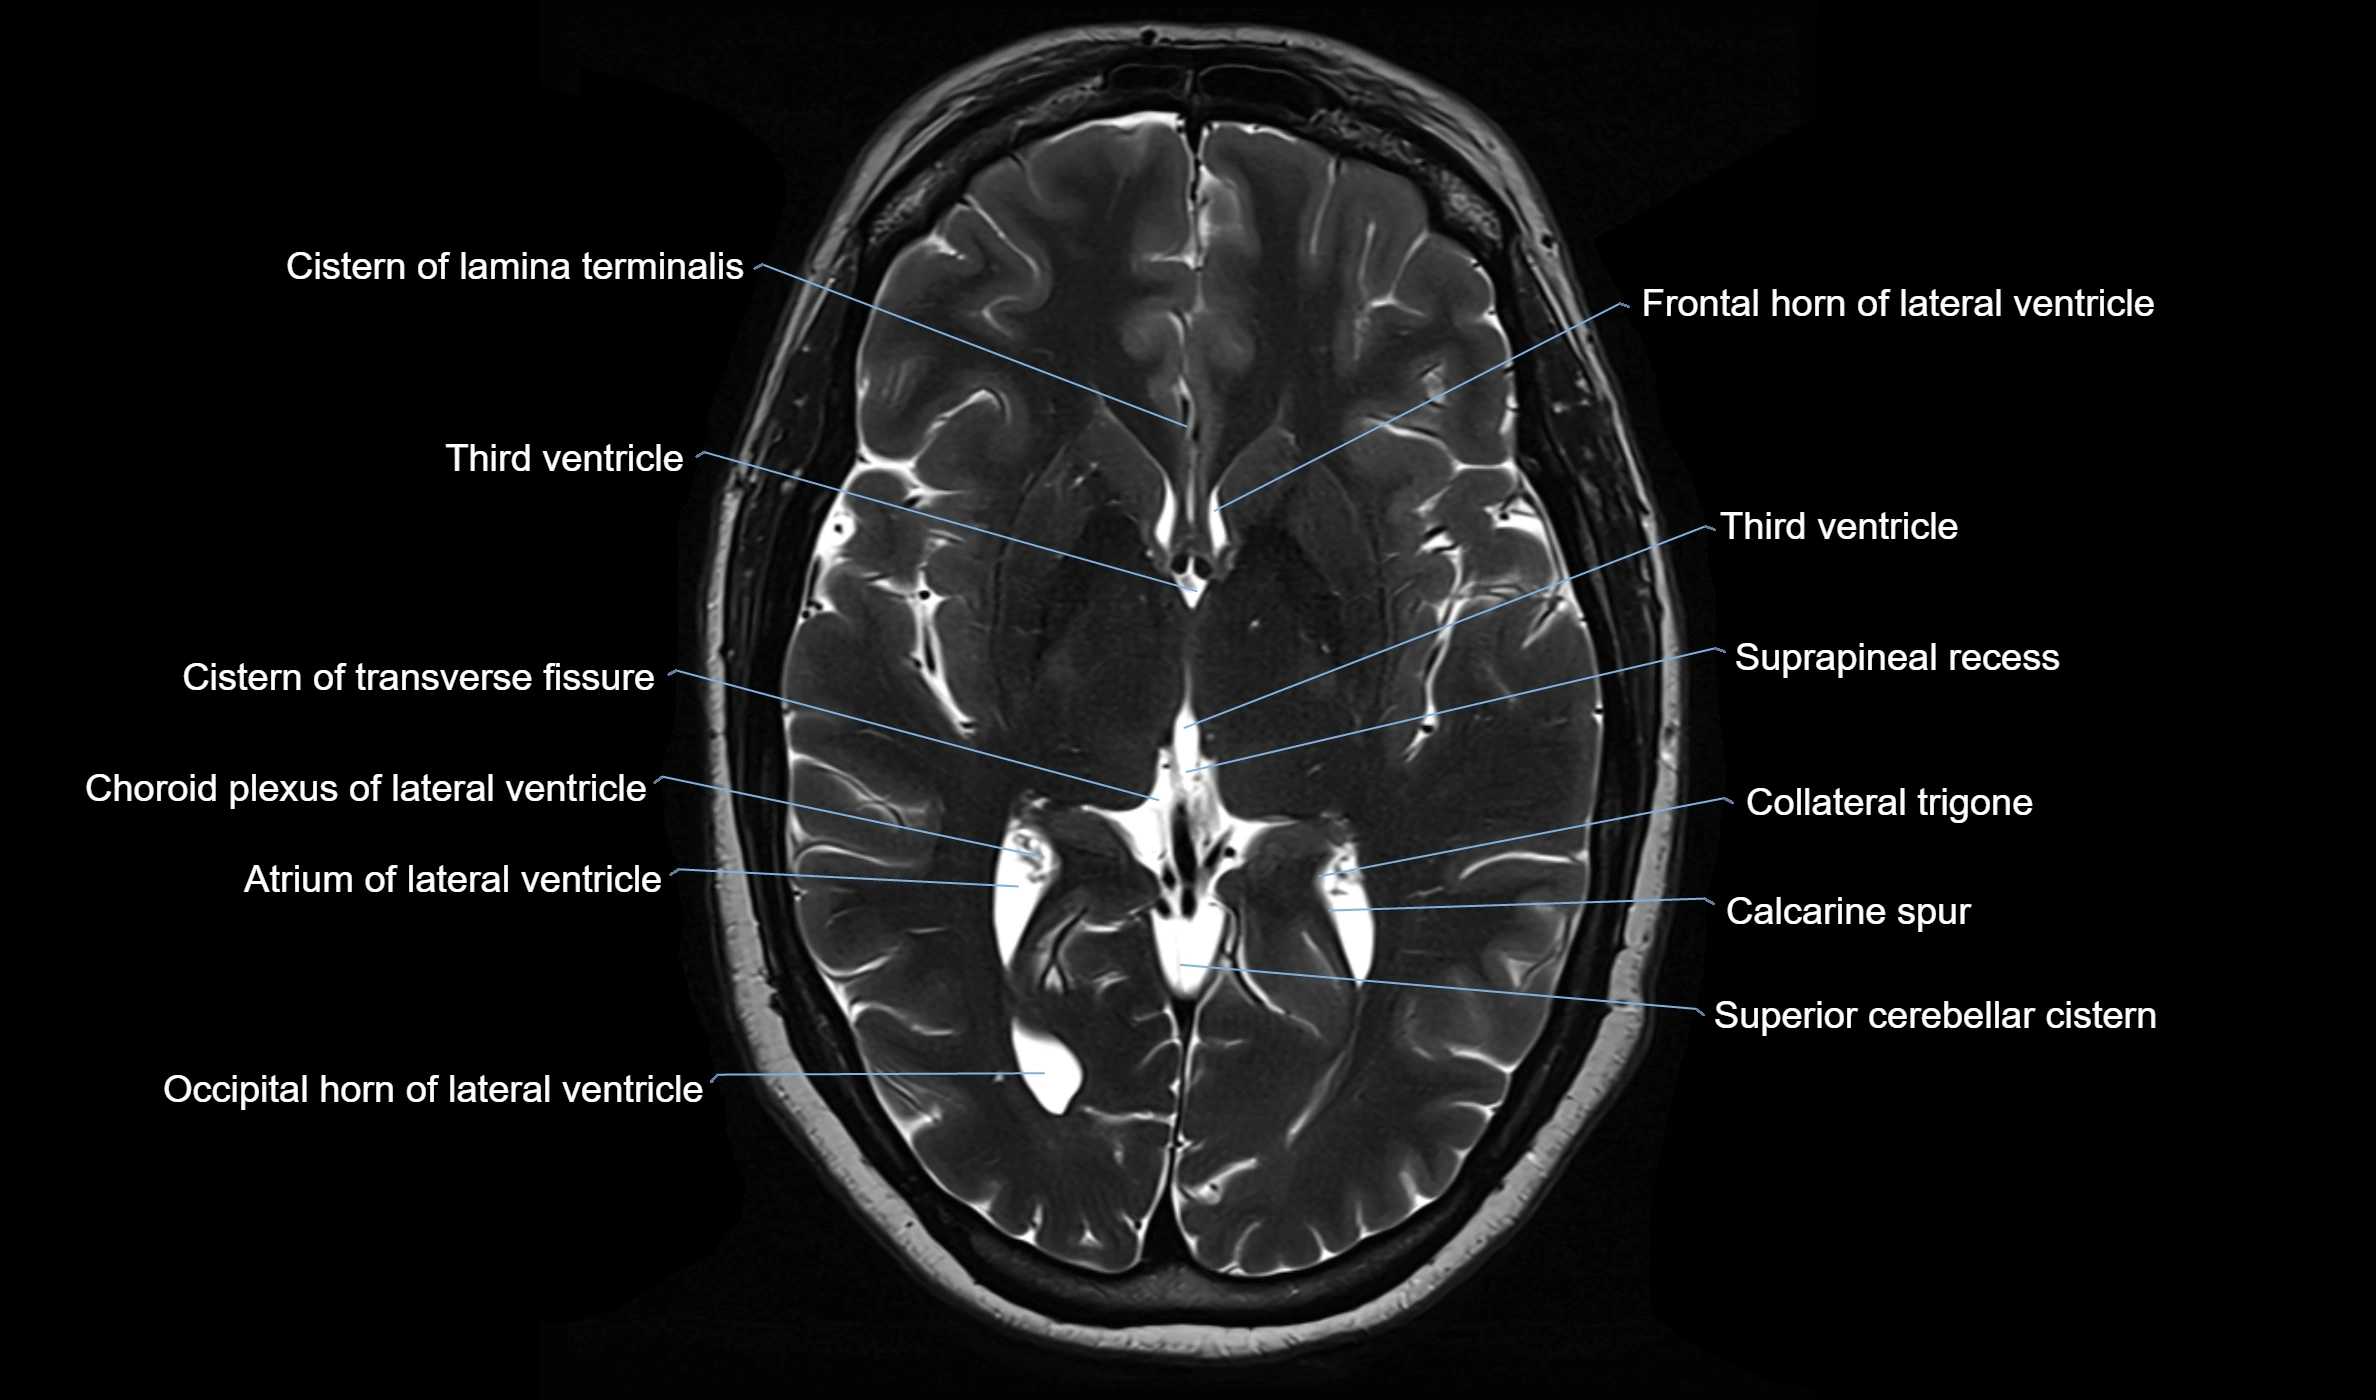

MRI images

image